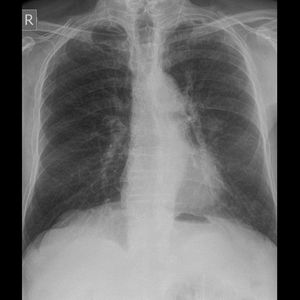

Chest X-ray

79 years old man with cough and dyspnea What is your diagnosis?

Aortic anurysm..?

Emphysma